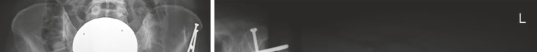

If the patient requires a derotational femoral osteotomy to correct the 36° anteversion, it is performed at this stage. A subtrochanteric osteotomy is executed, the femur is externally rotated to achieve a normalized anteversion of approximately 15°, and rigid fixation is achieved using a pre-contoured locking plate or a blade plate. Following the intra-articular and femoral work, the hip is reduced. The capsule is meticulously closed; a watertight closure is essential to prevent post-operative macro-instability and restore the proprioceptive function of the capsule. Finally, the greater trochanter is reduced and fixed using two or three fully threaded 4.5 mm cortical screws directed medially and slightly proximally toward the lesser trochanter.

Trochanteric non-union or delayed union is a more common complication, occurring in 1% to 3% of cases. It is often related to inadequate fixation, poor bone quality, or premature active abduction during the rehabilitation phase. Patients present with persistent lateral hip pain, a profound abductor lurch, and weakness. Management involves revision internal fixation, often augmented with bone grafting and tension band wiring. Heterotopic ossification (HO) occurs in up to 10% of patients, though clinically significant, motion-limiting HO (Brooker Class III or IV) is rare. Routine prophylaxis with non-steroidal anti-inflammatory drugs (e.g., Indomethacin or Celecoxib for 3-4 weeks post-operatively) is mandatory.